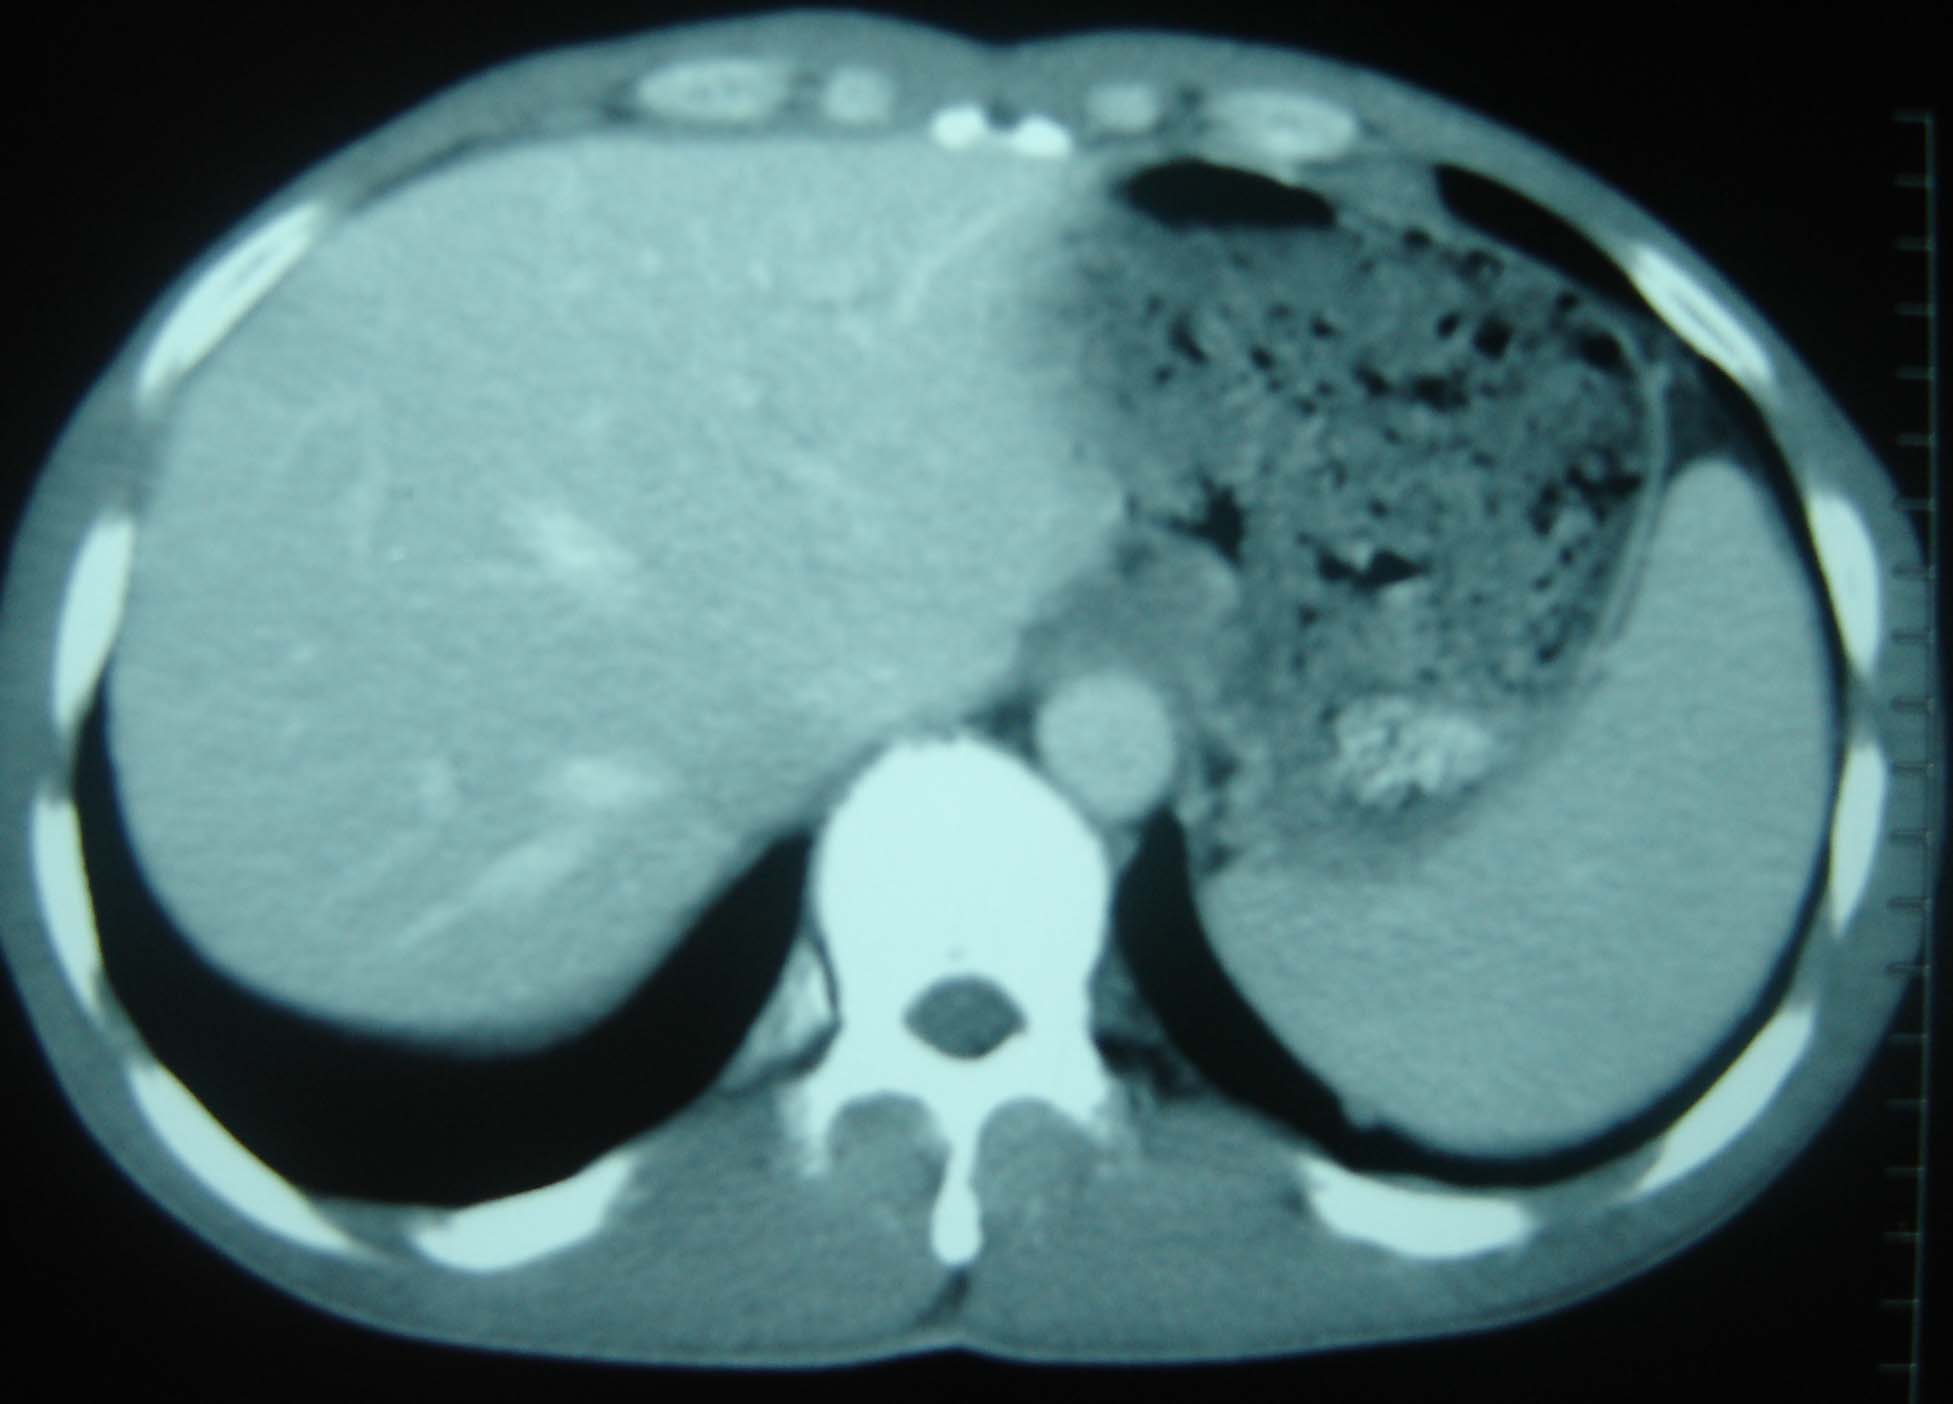

男 、43岁,咳嗽胸痛,装修工,平时接触粉尘较多,有吸烟史10多年,纤维支气管镜检查未发现异常,胃镜、腹部b超检查亦未发现异常,颈部淋巴结活检未发现肿瘤细胞。

1)考虑双肺及胸膜多发性转移瘤。2)肺气肿。